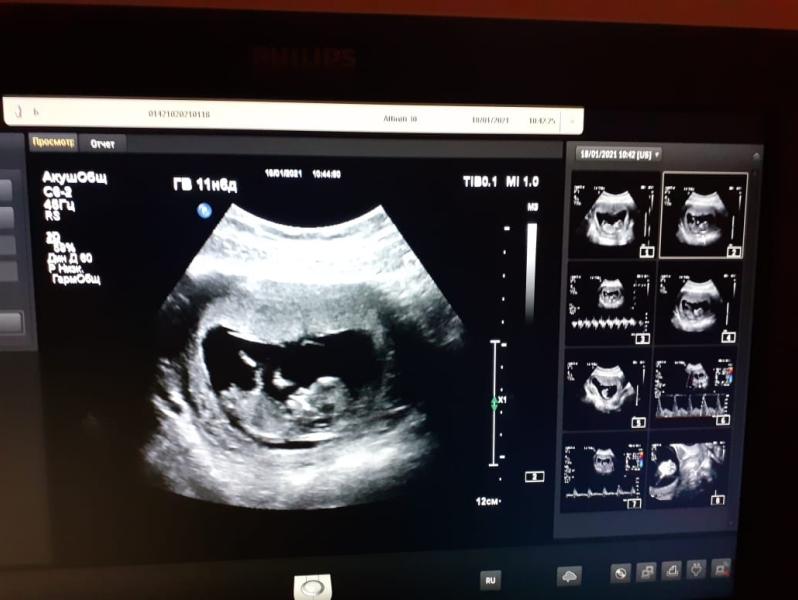

18.01. 1 скрининг

По параметрам плода все в норме, сдаю анализы, иду на прием к врачу....И тут звучит приговор:

- Шейка матки слишком короткая, каждые 10 дней будем делать цервикометрию (это узи шейки).

На тот момент шейка была 31 мм (норма около 40-45 мм)